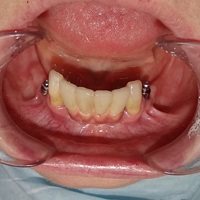

Pacjentka lat 58, prowadzi aktywne życie zawodowe. Odczuwała dyskomfort przy użytkowaniu protezy, dodatkowo przy uśmiechu odsłaniała klamry utrzymujące protezę.

Pacjentka lat 68, prowadzi aktywny tryb życia, dużo podróżuje, przeszkadzały jej klamry widoczne na zębach przy uśmiechu, oraz słaba stabilność protezy, co powodowało dyskomfort przy użytkowaniu.